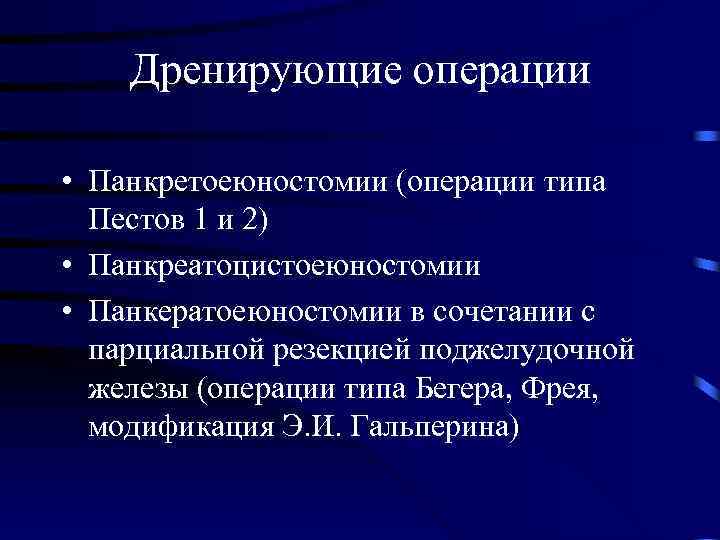

Дренирующие операции • Панкретоеюностомии (операции типа Пестов 1 и 2) • Панкреатоцистоеюностомии • Панкератоеюностомии в сочетании с парциальной резекцией поджелудочной железы (операции типа Бегера, Фрея, модификация Э. И. Гальперина)